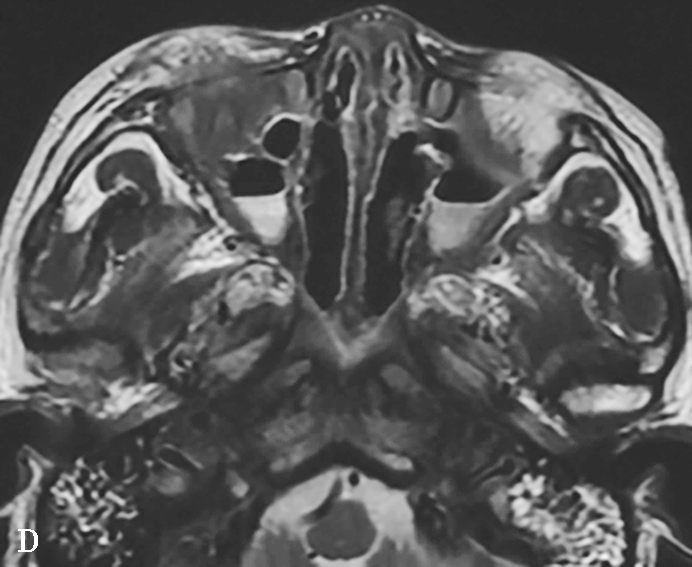

①平扫表现:首先侵犯鼻部中线区,鼻中隔和双侧中下鼻甲及上颌窦内壁骨质破坏,伴有不规则索条影;双侧上颌窦腔缩小,黏膜增厚,窦壁骨质硬化、肥厚,可出现“双线”征;最终导致上颌窦内壁、筛窦间隔、纸样板、筛板、鼻甲和鼻中隔明显破坏而形成大空腔,类似术后改变。鼻窦周围软组织浸润,眼眶是该病窦外侵犯的首发部位,很少累及颅底、翼腭窝、窦后区和鼻咽部(图1-3-26A、B)。②增强扫描表现:鼻腔及鼻窦可见结节状及肿块样黏膜增厚强化。

5.MRI表现

①T 1 WI表现:呈低至中等信号的结节状肿块影。②T 2 WI表现:早期T 2 WI多为高信号,中晚期多为结节状肿块影(与高信号的水肿黏膜相比),提示为纤维组织,当病变呈急性加重并侵犯邻近的软组织时,表现为软组织水肿高信号。③增强扫描表现:病变区黏膜呈结节状或肿块状强化,周围受累组织呈明显不均匀强化(图1-3-26C~F),TIC(时间-信号强度曲线)整体呈平缓型,早期缓升,说明GPA与TIC单纯表现为平缓型的普通良性病变相比血管通透性更高或血管数量更为丰富,致使对比剂早期更易透过血管进入血液,产生更高的流速造成早期时相内曲线斜率略升高,这与该病的多血管炎症的发病机制密切相关。

图1-3-26 鼻腔鼻窦肉芽肿性多血管炎

A、B.横断面CT及冠状面CT骨窗,示鼻背部塌陷,鼻中隔、双侧筛窦及上颌窦黏膜增厚,窦壁骨质增生硬化,内缘骨皮质欠光整;双侧中、下鼻甲形态欠自然,双侧眼眶内下壁骨皮质部分缺损,邻近内下象限肌锥外间隙可见弥漫性软组织增厚影,右侧为著;双侧上颌窦口-鼻道复合体增宽,钩突缺如;C.横断面T 1 WI,示双侧上颌窦腔可见略低信号,气-液平面可见,鼻背部塌陷,鼻中隔黏膜增厚,鼻咽顶后壁软组织增厚,呈等信号;D.横断面T 2 WI,示上颌窦腔病变呈高信号,余病变呈略低信号;E.横断面T 1 WI+FS+C,示窦腔、鼻中隔增厚,黏膜及其他受累结构呈中等强化,双侧翼腭窝及上颌窦后脂肪间隙受累,强化;F.冠状面T 1 WI+FS+C,示双侧眼眶内下象限肌锥外间隙病变呈中等强化,大脑纵裂及额部脑膜受累,呈弥漫性增厚强化